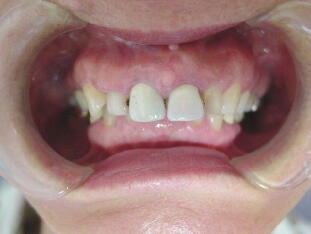

B、部分矯正の後、セラミック冠で治療した症例(上顎前歯部のみ治療)

![]() ![]() ![]()

奥歯のかみ合わせは比較的問題なかったので上の主訴のみ治療。上の前歯を治療するこ

とによって下の前歯も自然に良い位置に移動しました。歯並びを改善することにって歯肉 状態も改善されたことに注目してください。